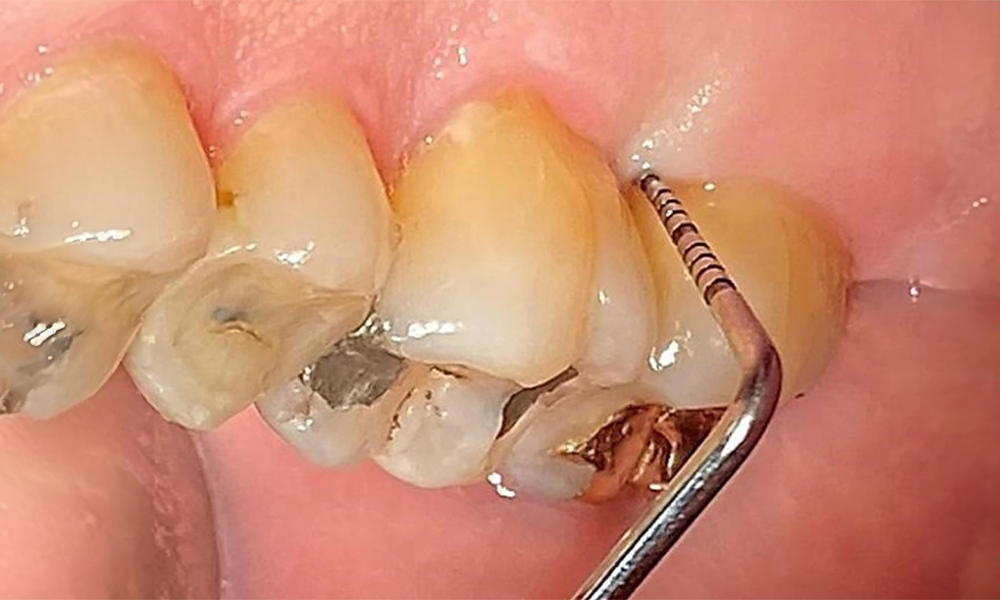

Right lateral view. Loss of the interdental papillae.

Fig. 3 Right lateral view. Loss of the interdental papillae. © Dr R. Krapf

The patient has a full dentition with 28 teeth, which includes amalgam and composite fillings in the molar and premolar regions. There is a visible clinical marginal gap present on tooth 14. Tooth 27 has an adequate gold inlay. There are also generalized attritions and abrasions. (Fig. 2, Fig. 3, Fig. 4, Fig. 5, Fig. 6)

The patient has stage II, grade B periodontitis (5). At 1 to 3 mm, the clinical probing depths were within the physiological range. Localized probing depths of 5 mm were observed on the mesiopalatal aspects on both 17 and 27. There are generalized recessions of 1–3 mm with partial loss of the interdental papillae (Fig. 2, Fig. 3, Fig. 4)